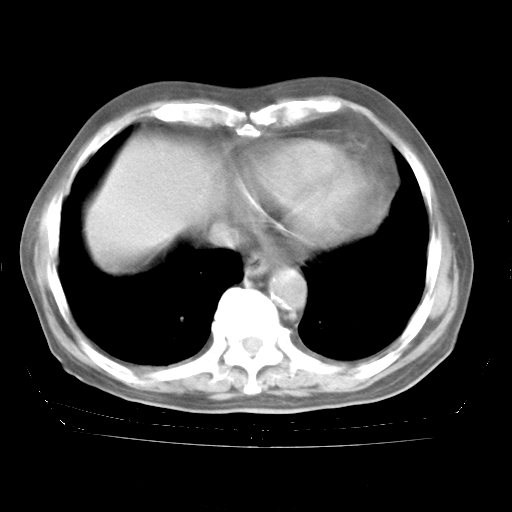

4月28日肺部CT——再次出现类似去年5月9日——透光度降低,“间质性”改变。

4月28日肺部CT

个人阅读4.14日肺部CT平扫:纵隔窗无异常,但肺窗示:双下肺内、后基底段有片絮状侵润影,部位以后基底段为著,以间质改变为主,呈急性肺泡炎征像,和首次住院影像学有相似之处。仅是个人读片,明日请相关专家再读片哈。其它建议同上。